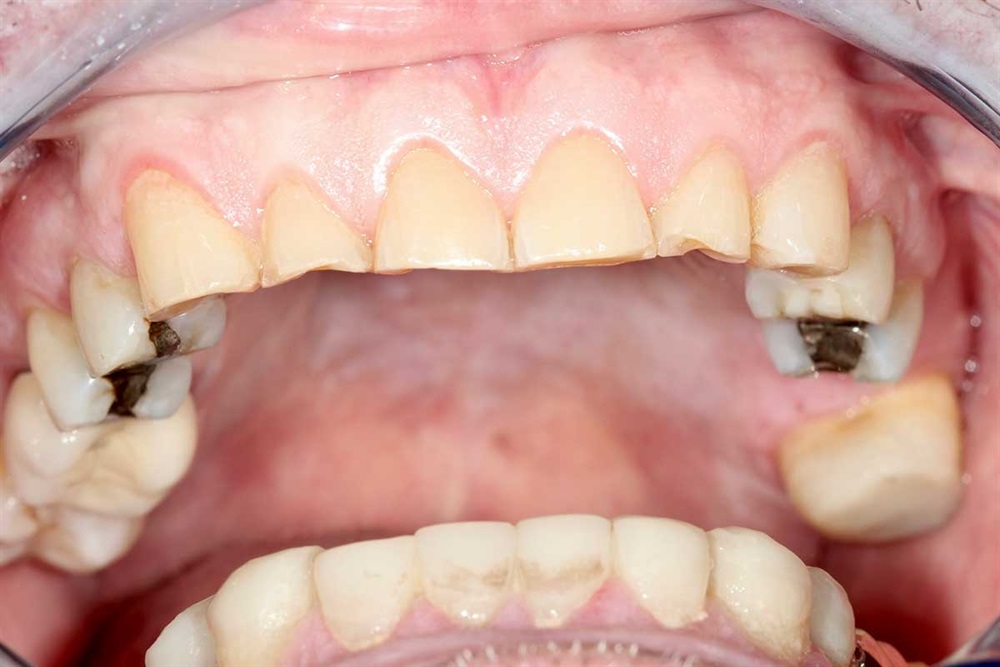

Fig. 1: June 2018. Where did all the tooth structure go? Grinding in protrusion? There is serious wear and tear. This 63-year-old gentleman has been wearing out his teeth, especially in the past 10 years.

Fig. 2: Maxillary teeth.